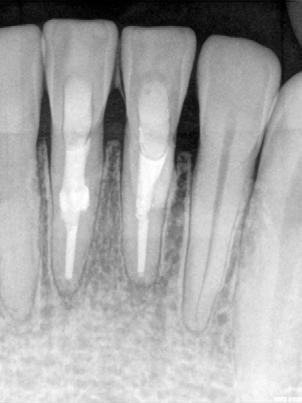

En la segunda sesión, 15 días después, realizamos la obturación convencional del tercio apical del canal con gutapercha, llenado de la cavidad reabsortiva con BIO-C ® REPAIR (Angelus, Londrina - Brasil) (Figura 7, 8 y 9), condensándolo contra las paredes con condensadores específicos y bolita de algodón humedecida y realizamos el sellado coronario con resina.

El BIO-C® REPAIR es un cemento reparador biocerámico listo para su uso. Se compone de silicato de calcio, aluminato de calcio, óxido de calcio, óxido de zirconio, óxido de hierro, dióxido

de silicio y agente de dispersión. El BIO-C® REPAIR presenta características superiores de adaptación marginal, biocompatibilidad, excelente radiopacidad y capacidad selladora en ambientes húmedos. Además de estas características, tiene como gran ventaja su facilidad de inserción a la cavidad reabsortiva

8 - Radiografia final

9 - Cavidad reabsortiva rellenada com BIO-C® REPAIR